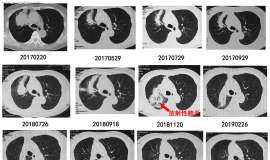

肺腺癌:奥希替尼耐药后盲试靶向药,肝转移消失,胸腔积液增多,求助下一步治疗方案!

病人72岁,肺腺癌确诊3年,奥希替尼耐药,培美+顺铂+依沃西化疗四次后,胸腔积液增多,肝多发转移瘤,医生建议用芦康沙妥珠单抗,考虑病人化疗后体质差,盲试靶向药三个月,体感变好,复查后肝转移瘤消失,CEA增涨, ...